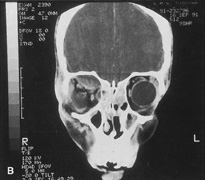

The transcranial orbitotomy uses a frontal craniotomy with removal of a portion of the orbital roof to expose the orbital apex or superior orbit. This is best performed by a neurosurgeon familiar with skull-base surgical approaches. In most cases, the supraorbital rim over the involved side is removed en bloc with the frontal bone flap (Fig. 13). The anterior one-half or two-thirds of the orbital roof breaks free with removal of the rim and frontal bone flap, and the remaining posterior portion of the roof can be removed with rongeurs. Historically, it was suggested that all orbital tumors be removed via craniotomy, because before the imaging era it was difficult to anticipate the intraorbital location of a mass.18 The transfrontal approach was first described by Jones10 in 1970. Jane and colleagues19 proposed the current technique in 1982. Refinements have been discussed by Maroon and Kennerdell9 and Housepian.20 This operation has been termed the panoramic orbitotomy by Rootman21 because of the wide area of exposure offered by this procedure.

Fig. 13. Schematic diagram for transcranial orbitotomy in which the supraorbital rim is removed en bloc with the frontal bone flap. This provides extensive exposure to the superior and lateral orbit.

Fig. 14. A,B. Large intraorbital lymphangioma causing proptosis and optic nerve compression in a 2-year-old child. C. View of the left orbit from above after removal of the frontal bone flap, including the supraorbital rim and orbital roof. An extensive exposure of the entire superior and lateral orbit is afforded. The levator and superior rectus complex is being retracted laterally with a muscle hook, whereas the Freer elevator retracts the superior oblique muscle medially. The frontal nerve can be seen running from posterior to anterior over the superior orbit. The orbital mass is exposed in this fashion. D. The fronto-orbital bone flap is wired back in place after completion of the procedure. E. Postoperative appearance of the patient. F. The postoperative CT scan shows complete removal of the lymphangioma. This large and diffuse lesion would have been difficult to remove with any other approach.

A burr hole is placed in the midline just above the orbital rim. This burr hole usually enters the frontal sinus. A second burr hole is placed anteriorly in the temporalis fossa at the junction of the cranium and orbit so that both compartments are exposed. Two or three additional holes are made in the frontal bone connecting the first two holes. The orbital rim is cut from the midline inferiorly, and the lateral orbital rim is cut from the temporalis fossa anteriorly. The dura is freed from the undersurface of the bone flap and is elevated superiorly, and the orbital roof is cracked off. The frontal bone, orbital roof, and supraorbital rim break off in one piece. The brain is retracted superiorly, and the remaining orbital roof is removed with bone rongeurs (see Fig. 14C).

After removal of the bony roof, the periorbita is visible. Typically, the periorbita is thin, and the levator rectus muscle and frontal nerve are visible beneath it. If exposure of the posterior optic nerve is desired, the dura can be elevated over the optic canal. The canal can be unroofed to decompress or explore the optic nerve, and the dura may be opened to view the intracranial optic nerve and the chiasm. At the orbital apex, the annulus may be cut to allow more anterior dissection and removal of the optic nerve in cases such as optic nerve glioma or meningioma. Because the superior orbital fissure and its contents lie lateral to the nerve, the intraconal space is entered on the medial side of the optic nerve. The orbital dissection can be carried out with a minimal amount of brain retraction after the en bloc removal of the frontal bone, supraorbital rim, and orbital roof.

After the dissection, the dura is closed and the frontal bone flap is plated or wired back into position (see Fig. 14D). The orbital roof is functionally restored with the replacement of the bone flap. The sinuses must be sealed off with muscle, pericranium, or other tissue. The coronal flap is closed in layers. The postoperative appearance is unchanged because the bone flap is replaced in one piece. Problems with globe ptosis, enophthalmos, pulsatile proptosis, or meningitis are rare. However, extensive mobilization of the temporalis may result in cosmetically significant temporal atrophy. Orbital apical dissection often results in extraocular motility dysfunction as a result of traction on the third, fourth, or sixth cranial nerves, but cranial nerve function usually recovers unless the nerves have been transected.